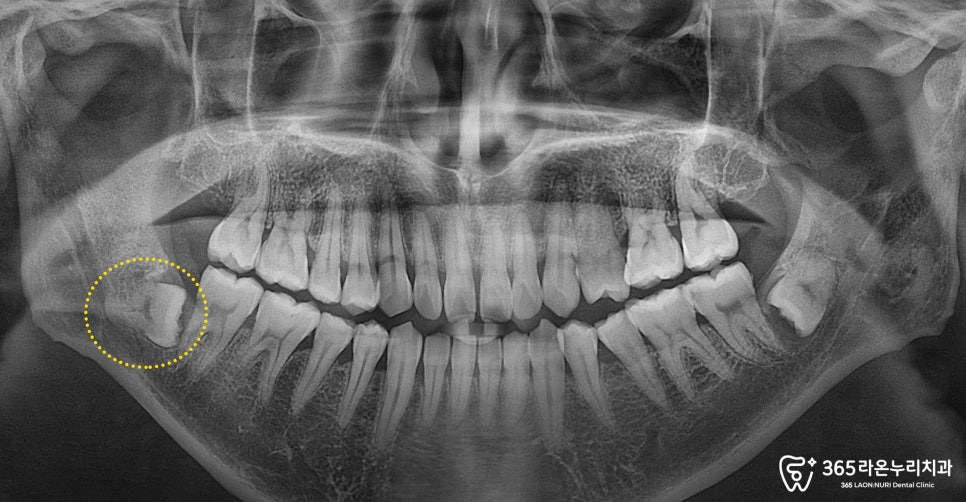

신장동 치과 에서는 좀 더

자세한 확인을 위해 엑스레이를

촬영해보기로 했습니다.

그러자 엑스레이 사진에서

치아가 매복되어

누워 있는 모습이 관찰되었습니다.

이처럼 치아가 누운 상태로

자라면 앞쪽 어금니를 지속적으로 밀어냅니다.

이 과정에서 신장동 치과 에서는

치아 뿌리에 압력이 가해져,

신경이 자극되면서 지속적인 통증이

나타난 것으로 확인하였습니다.

그리고 매복 사랑니가

아래에 흐르고 있는 하치조 신경과

완전히 겹쳐져 보이는 판독

결과를 볼 수 있었습니다.